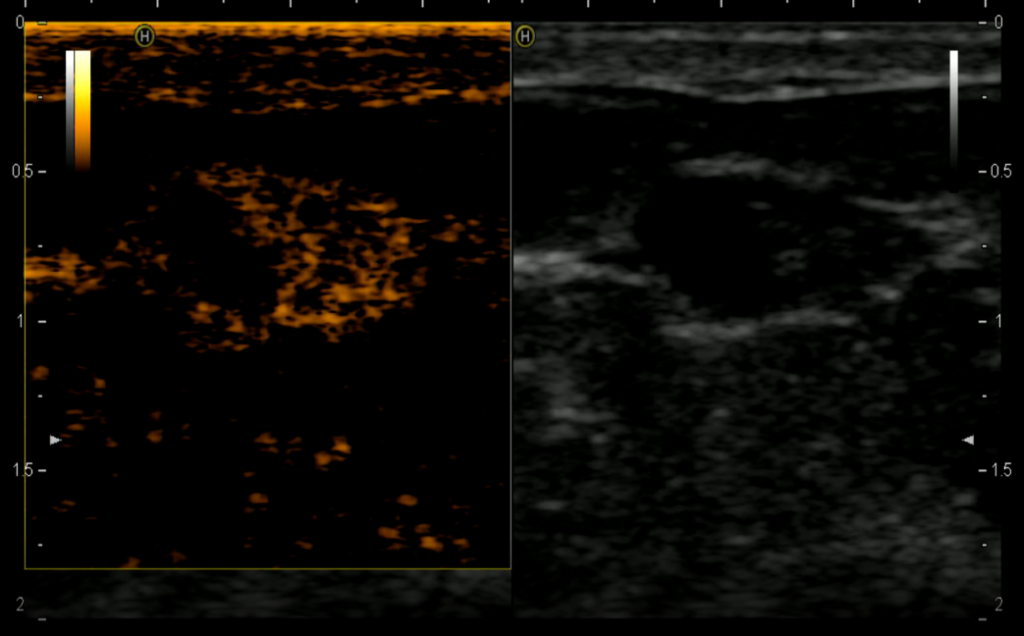

Допплеровский режим определяет кровоток. Важная технология, которая позволяет врачу увидеть сосудистую сеть патологического образования без введения контрастного вещества. Конечно, Допплер не такой чувствительный режим, как контрастирование, но в большинстве случаев он дает важную информацию и способствует раннему выявлению рака.

Рис.8 Эхограмма гиперваскулярного рака молочной железы

Рис.9 Эхограмма гиперваскулярной фиброаденомы молочной железы